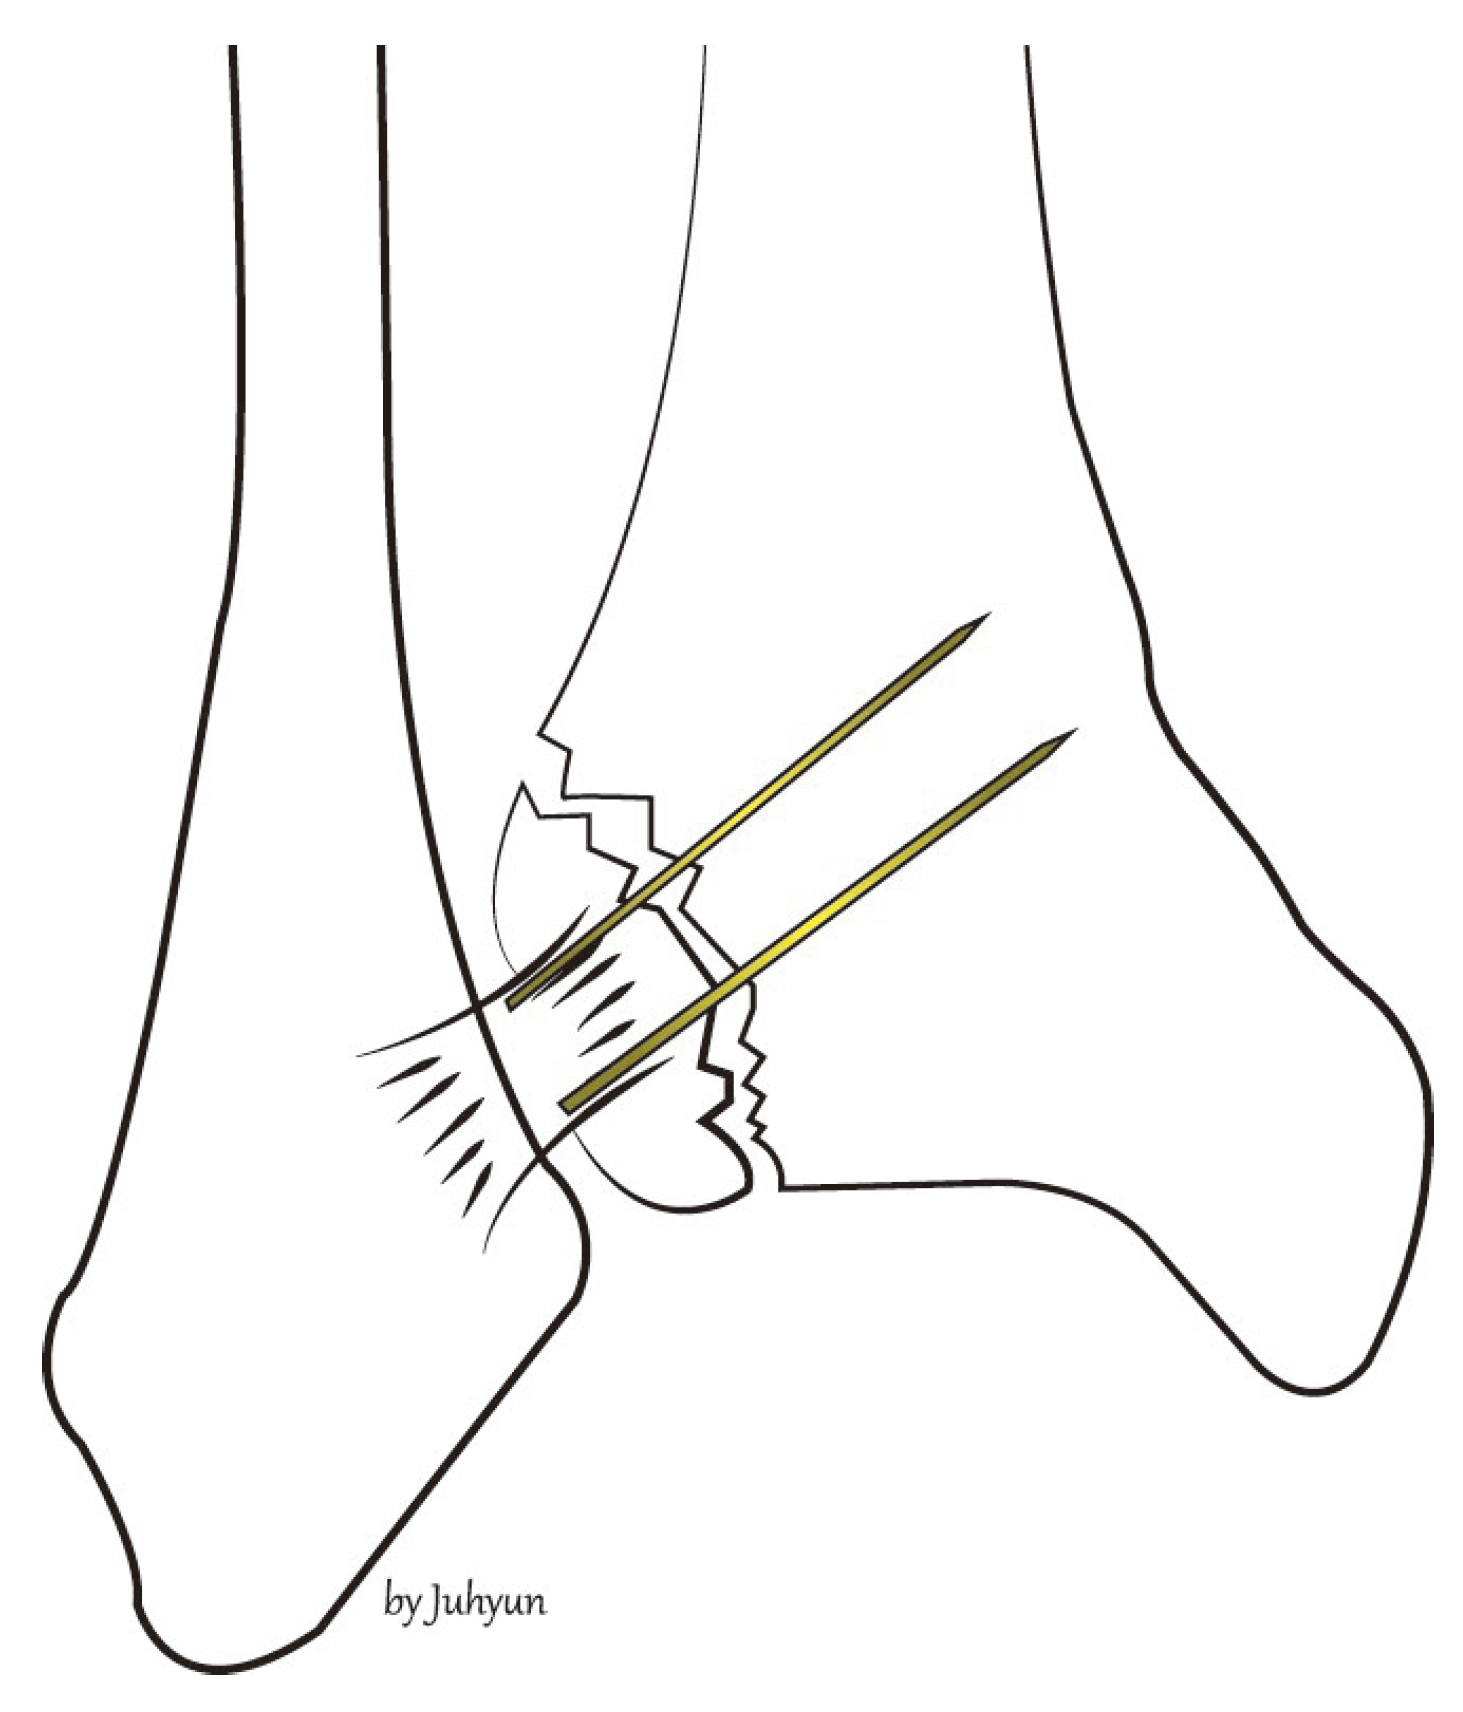

2. Surgical Technique